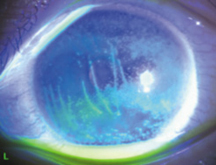

コンタクトレンズを使用して角膜が酸素不足になると、角膜の周囲から中央に向けて血管が侵入してきます。

これを角膜新生血管(パンヌス)と呼びます。

ハードコンタクトレンズよりソフトコンタクトレンズのほうが角膜を覆う面積が大きいためにこの状態が起こりやすく、特に酸素透過性が低いレンズを長時間装用することはよくありません。

角膜新生血管は黒目に侵入してくると視力が出づらくなり、更に悪化すると失明の危険性も出てきます。

血管の侵入が著しい場合には、酸素透過性のよいレンズやハードコンタクトレンズに変更するか、眼鏡に変更し十分に酸素を補います。